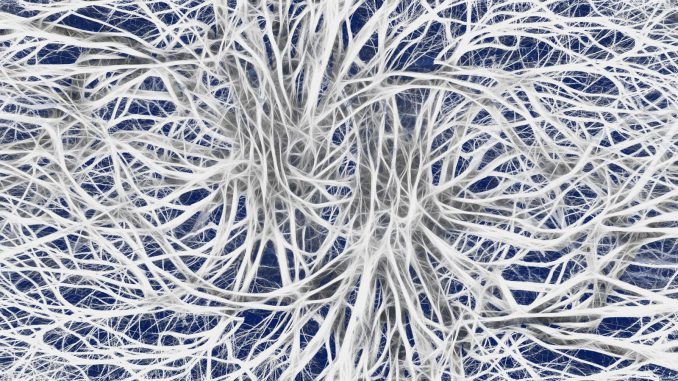

Patients with Parkinson’s suffer from massive loss of nerve cells in a brain region that’s normally packed with dopaminergic neurons. Dopamine allows brain cells to transfer messages and orchestrate motor actions.

“Parkinson’s disease patients have a severe neuronal cell death that is more specific to areas in the brain that are compacted with dopaminergic neurons,” she says.

Stern is creating 3D structures that approximate one of these brain areas, as an innovative approach, to evaluate potential treatments such as dopamine receptor modulators.